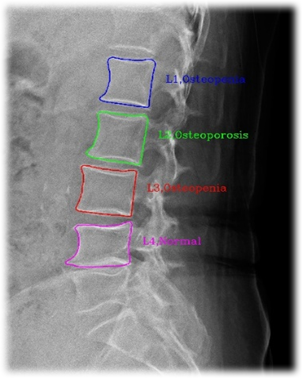

3. 라벨링

| 3 | class | str | Y | 척추체 번호 및 질환 코드 | 척추체 번호: L1-L4 | Exception은 | |||||

| 질환 코드: Normal, Osteopenia, Osteoporosis, Exception | 척추 영역 | ||||||||||

| 1 | color | str | Y | 레이블 시각화 색깔 | |||||||

| type | str | Y | 레이블 타입 정보 | polygon | |||||||